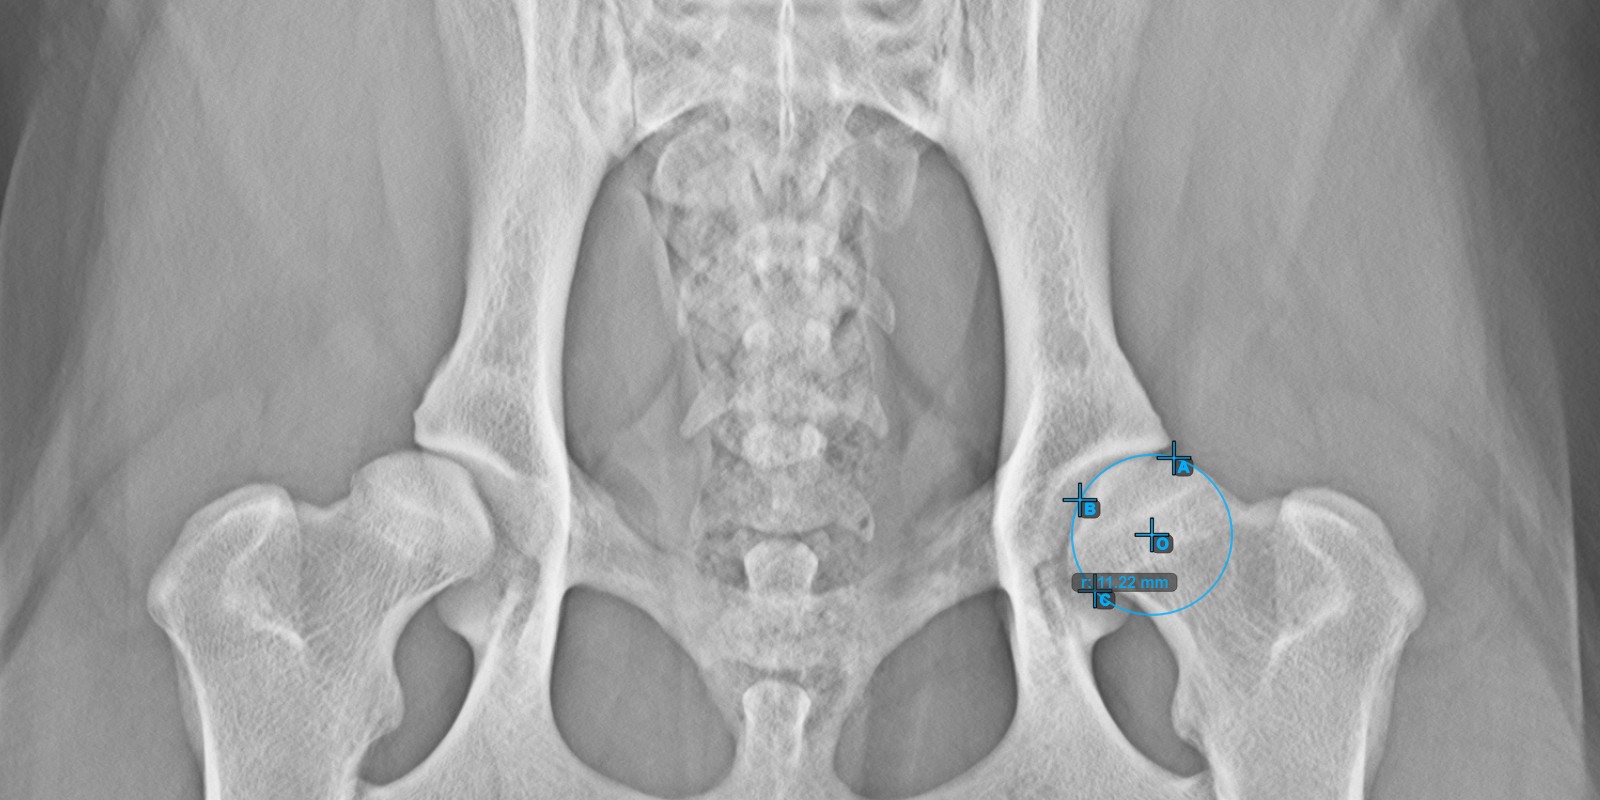

Start the measurement by marking the three points on the articular surface of the left Caput Femoris.

Mark the three points on the articular surface of the left Caput Femoris (outside of the Fovea Capitilis). Regardless of the order, make sure to mark the most cranial point, the most caudal point and the midpoint of the femoral head. A circle will be automatically constructed based on the three placed points.

The image below depicts the typical placement of the three points on the articular surface of the left Caput Femoris.